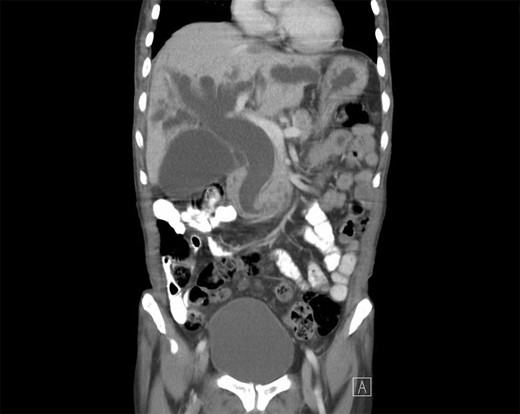

The patient is a 63-year-old Chinese male who presented with lethargy, 10-pound weight loss and painless jaundice for 1 week. Patient had a prior episode of jaundice of unclear etiology 2 years prior treated medically and had just emigrated from China 1 month prior to admission. Patient was febrile to 102.4°F, jaundiced with a total bilirubin of 18.5 mg/dL. Abdominal ultrasound showed intra and extrahepatic bile duct dilation, the distal CBD was dilated to 25 mm. Patient underwent endoscopic retrograde cholangiopancreatography (ERCP), which showed thick yellow mucus and no stones (Fig. 1). A sphincterotomy was performed and a pigtail stent placed. Computed tomography (CT), magnetic resonance imaging and magnetic resonance cholangiopancreaticogram failed to show a pancreatic head mass, distal CBD mass or stones causing obstruction (Fig. 2). Cold forceps biopsy of the papilla, endoscopic ultrasound with fine needle aspiration biopsy (FNAB) of pancreatic head, and CBD brushings were all nondiagnostic. CBD stents occluded two times in 2 weeks’ time secondary to thick mucus, requiring multiple ERCPs with stent exchanges (Fig. 3). After extensive multidisciplinary discussions regarding unclear etiology of distal CBD obstruction and extensive discussion with patient and family, the decision was made to perform a Whipple procedure for diagnosis and definitive treatment. Intraoperatively, choledochoscopy was performed, which showed very thick yellow mucus and frond-like mucosa near the ampulla. Final pathology showed a 2.0 × 1.5 × 0.5 cm3 granular lesion in the distal CBD. There was prominent biliary epithelial proliferation with tubular–papillary architecture and minimal nuclear atypia in association with chronic inflammation, stroma reaction and smooth muscle proliferation. The overall histological change in the distal CBD resembled that of AH seen in gallbladder, likely non-neoplastic change (Figs 4 and 5). At 1 year follow-up, he is doing well and his jaundice has resolved.

Repeat endoscopy 1 week after ERCP with sphincterotomy and stent placement shows thick mucus obstructing CBD.